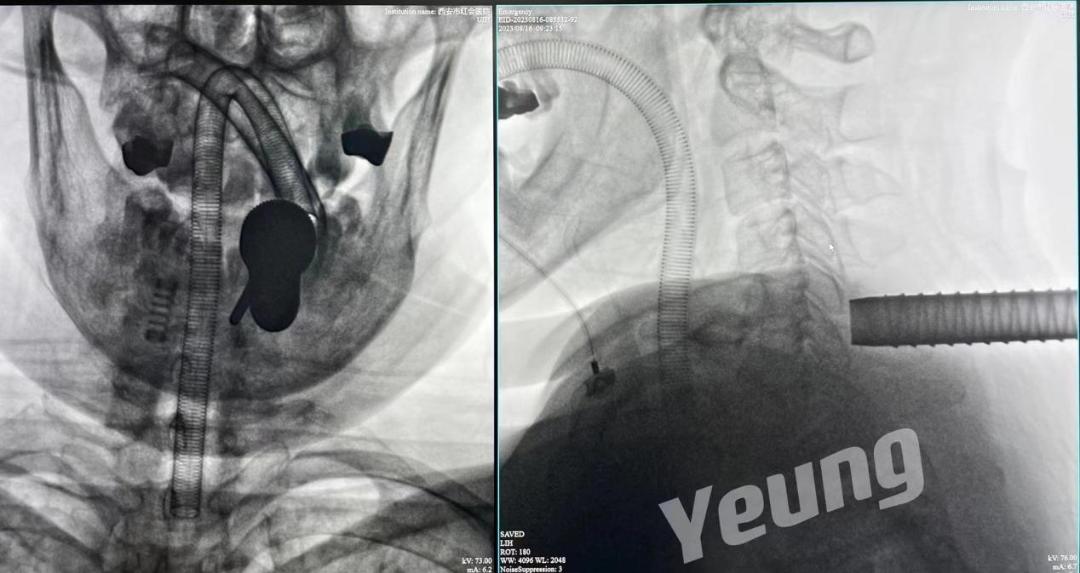

穿刺定位

置入内镜通道

显露“V”点

“钥匙孔”后术区

减压完成

微创手术切口1cm左右

手术结束后当天患者症状明显缓解。复查影像资料显示神经减压良好、骨赘完全去除。

术后影像资料